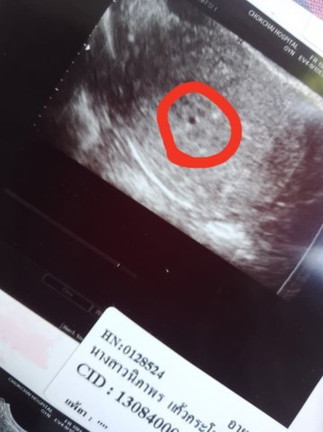

ใช่ถุงการตั้งครรภ์ไหมคะ หมอบอกว่า4สัปดาห์ มีเลือดออกหมอบอกปกติของการฝังตัวอ่อน🥹แม่กังวลมากค่ะกลัวน้องไม่อยู่ด้วย